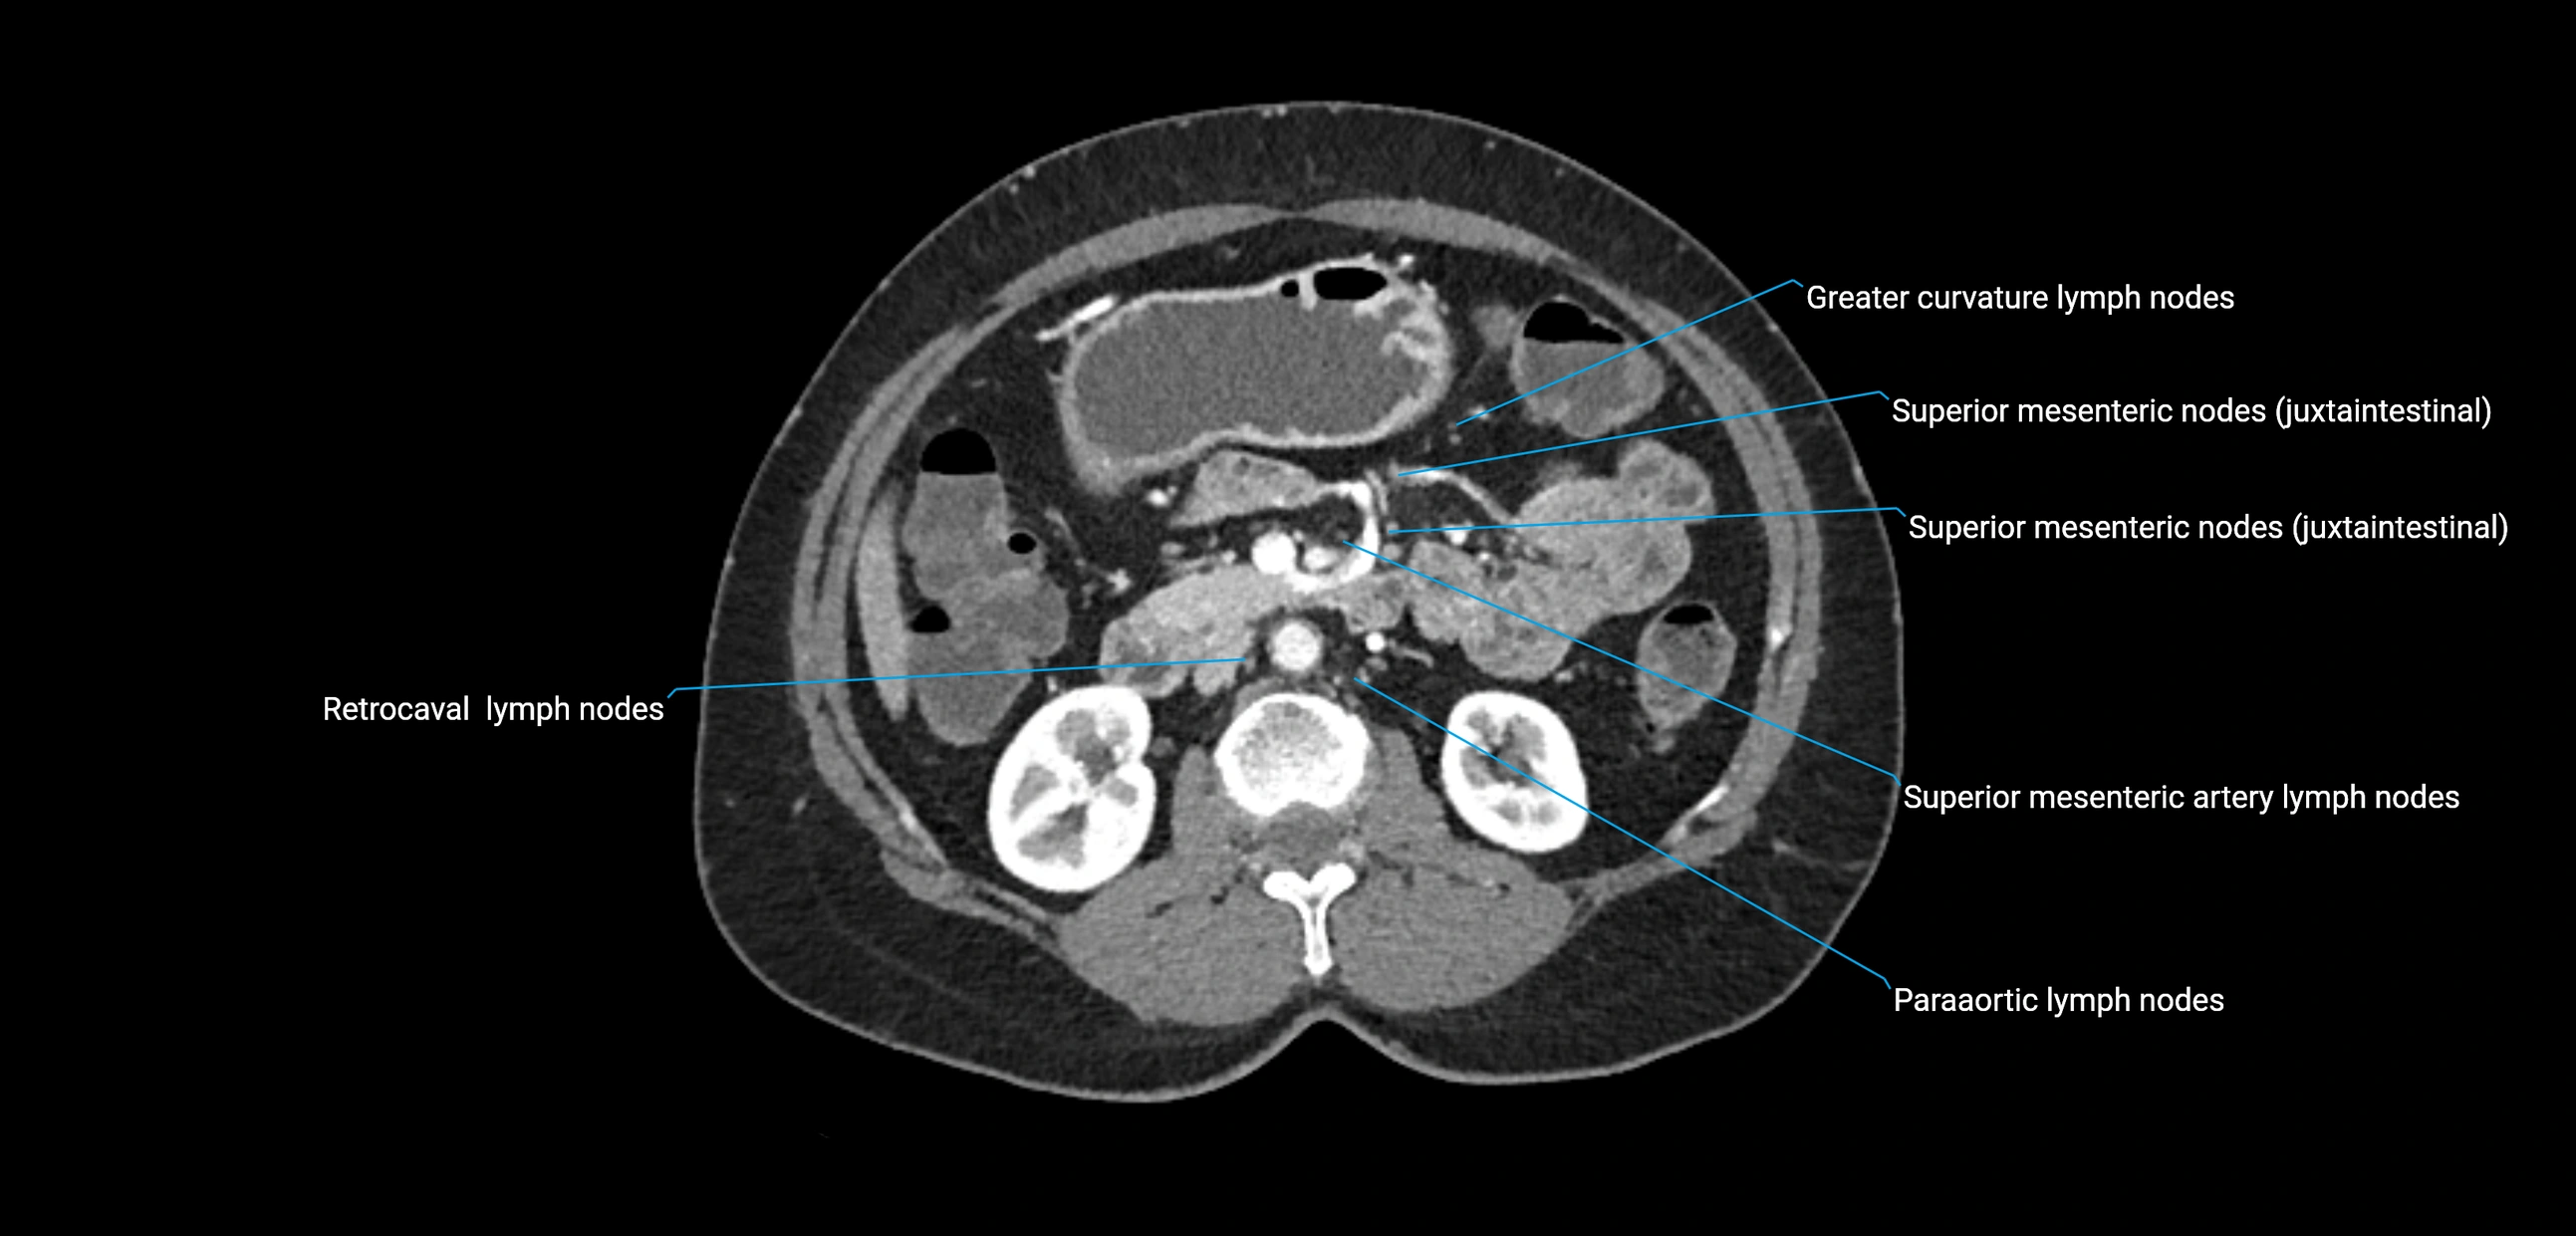

CT image

image